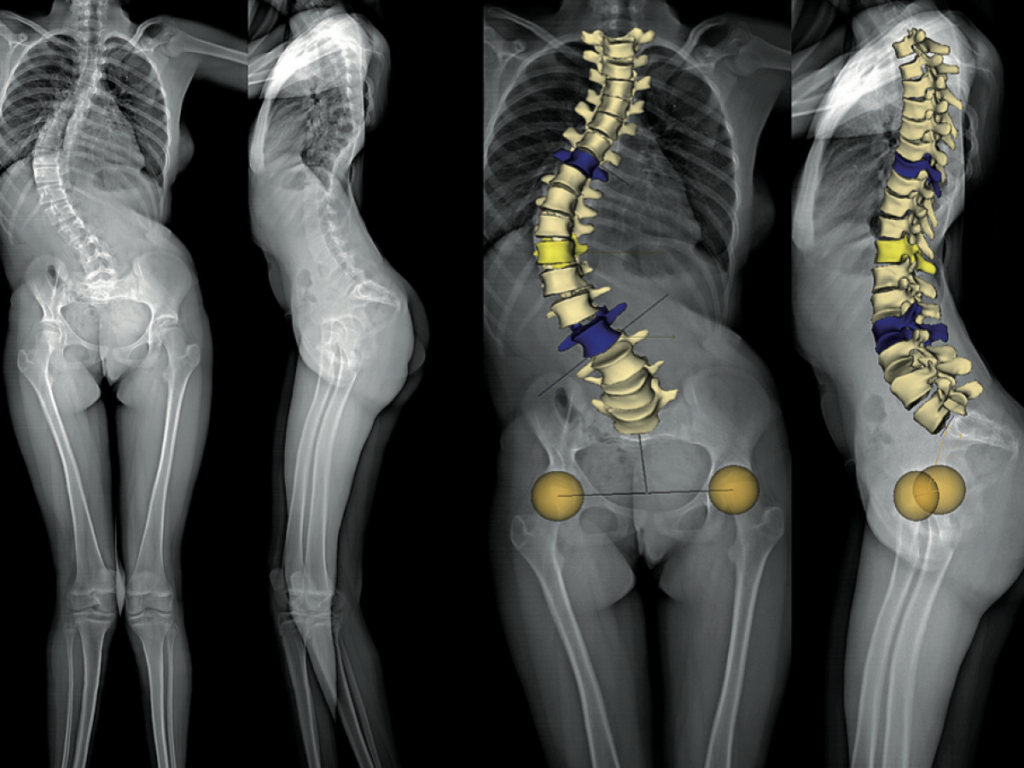

On parle de scoliose quand « la colonne vertébrale est penchée sur la droite ou sur la gauche avec ou sans apparition de légère bosse, lorsqu’on regarde la personne de dos » explique Naomie Adammado. Pour la kinésithérapeute, il existe différentes types de scoliose : la scoliose idiopathique (la plus fréquente avec environ 80%des cas), la scoliose congénitale ( c’est à dire à la naissance), la scoliose syndromique (d’origine neuro musculaire), la scoliose secondaire (suite au traumatisme ou à un cancer), la scoliose dite de Novo qui fait suite à une dégénérescence du rachis avec l’âge et la scoliose d’attitude (un positionnement préférentiel dû à la douleur, qui peut faire pencher le haut du corps par ricochet la colonne vertébrale).

La spécialiste informe que plusieurs options sont possibles. Il y a un diagnostic fait à la maison : « C’est à dire repérer  les côtes qui ne sont pas identiques » ; « Faire pencher la personne vers l’avant et observer la courbure du dos » ; Ou soit « Debout les pieds joints et les bras pendant, voir si il y a une différence d’écart entre chaque bras et la taille ». Une fois que tout ceci est confirmé, poursuit-elle « aller à l’hôpital, pour un diagnostic établit avec l’aide d’un médecin, par : Un examen physique et une radiographie »